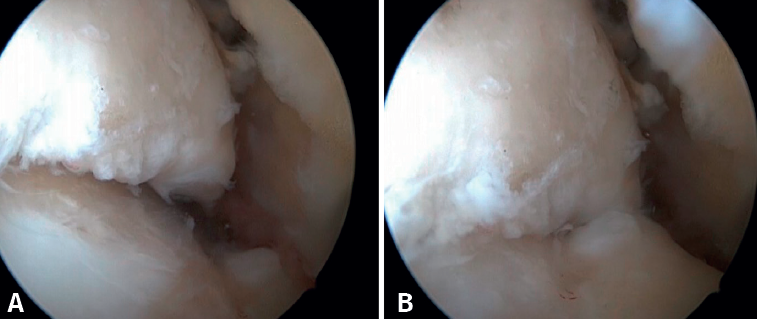

Figure 1. Bony impingement between the talus and tibia. A: ankle in plantar flexion; B: ankle in dorsiflexion showing impingement between the two osteophytes.

Figure 2. Anterior tibial osteophyte. A: in dorsiflexion the capsule separates from the osteophyte allowing its resection (B) through reaming.

Figure 3. Osteophyte due to chronic instability. A: the osteophyte forms a bone block extending over the anterior margin of the tibial plafond and the anterior aspect of the medial malleolus; B: arthroscopic view.